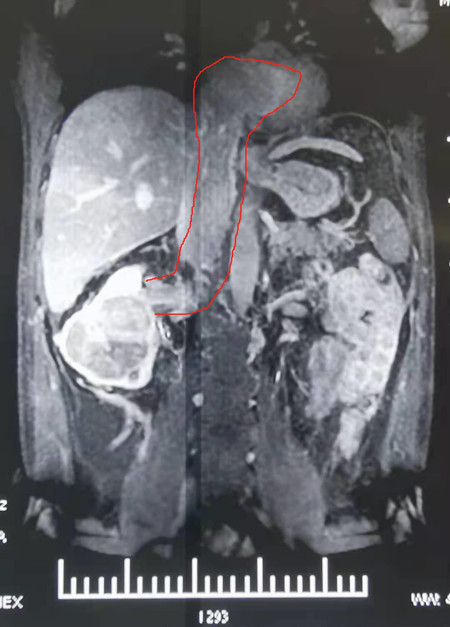

患者梁XX,男,42岁,因“胃胀伴双下肢水肿3月余,体检发现右肾恶性肿瘤伴下腔静脉瘤栓”入院。入院后完善相关检查提示:下腔静脉瘤栓,长约15cm,上端进入右心房,心脏彩超示右心房内可见4.5*3.0 cm低回声团块。入院诊断为:右肾恶性肿瘤伴下腔静脉IV级瘤栓。

为最大程度的降低手术风险,MDT团队反复探讨手术方案,打磨手术细节,针对术中可能出现的风险及意外准备相应的应急预案,制定了周密而详细的术前准备、手术步骤与计划。考虑该患者瘤栓较长,且突入右心房部分体积较大,可能存在取栓时离断脱落可能。种铁教授决定拟实施开放手术切除肾脏及游离暴露腔静脉、左肾静脉、肝血管及腰静脉,同时行体外循环辅助下下静脉瘤栓取出术。